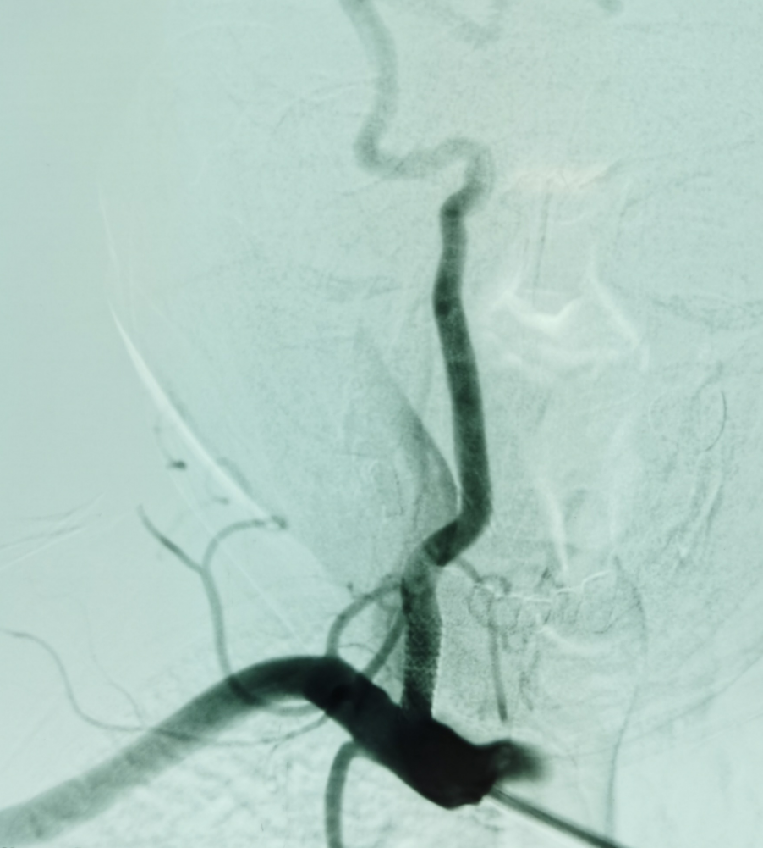

患者盛某某,因反复发作性头晕多次入院,完善CTA示左侧椎动脉狭窄,应用多种药物效果欠佳,魏华明主治医师考虑为椎动脉狭窄所致后循环缺血,给予椎动脉支架植入血管成形术,术后头晕症状完全消失。

左侧椎动脉狭窄

椎动脉支架

植入血管成形术